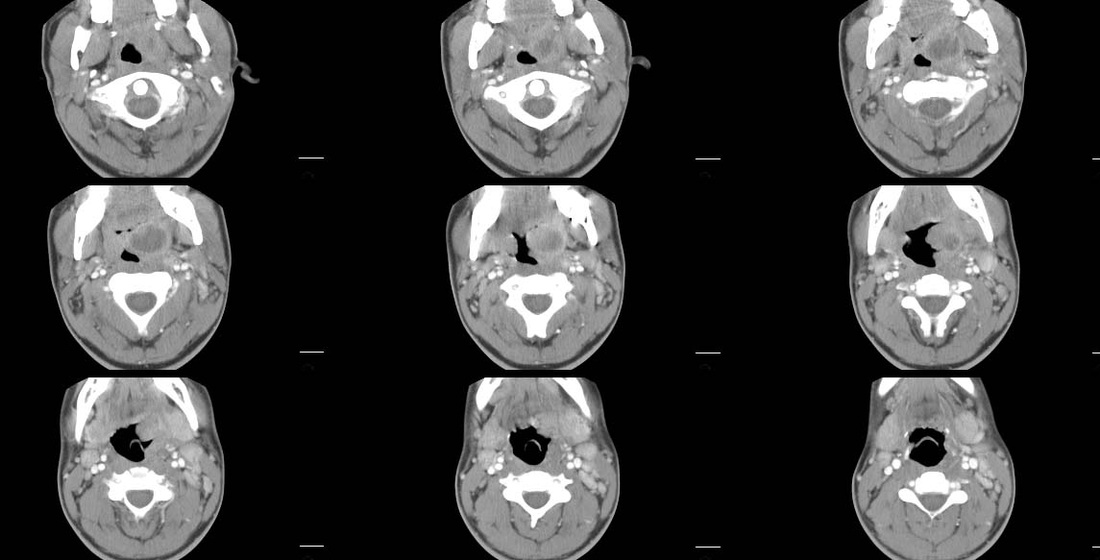

There is a focal oval left parapharyngeal lesion which produces marked pharyngeal narrowing by compressing but not invading/eroding into the airway. The lesion demonstrates low attenuation centrally with peripheral enhancement.

The appropriate treatment would depend on the correct diagnosis. In this instance the patient had associated febrile illness which suggested a diagnosis of a left palatine tonsillar abscess. Also the cystic appearance produced by the pus centrally on the CT scan favour an abscess over most neoplams which would demonstrate more solid density.